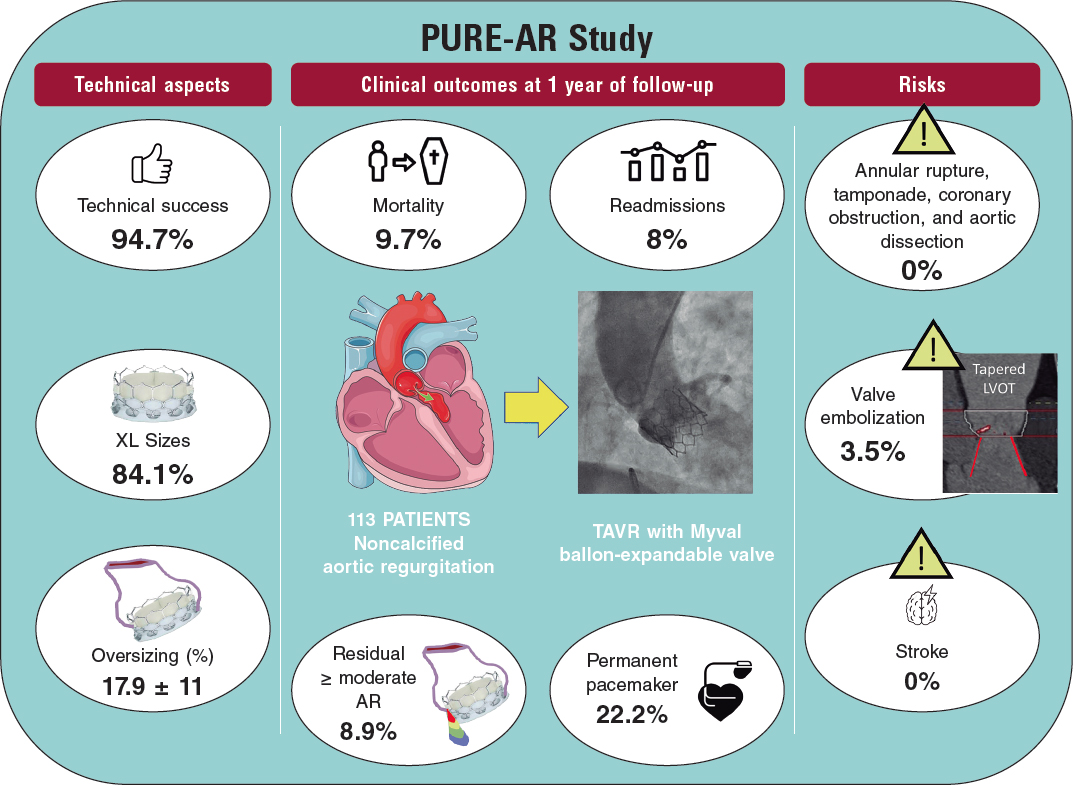

Current data confirm that repairing the TV while performing left heart cavity surgery is safe. However, reinterventions due to persistent TR are associated with high morbidity and mortality rates.6 Recent studies show that isolated TV surgery is still the valve surgery that is most associated with higher surgical risk and mortality rates between 8.8% and 9.7%.7 Therefore, the percutaneous therapies for the management of TR are an alternative to conventional surgery for patients who, until recently, were eligible for conservative medical treatment only for being high surgical risk patients.

Depending on the repair anatomical target, devices can be divided into coaptation, valve annuloplasty, and replacement devices (whether in the orthotopic or heterotopic position). The most widely used technique is the edge-to-edge repair with the MitraClip device (Abbott Vascular, Santa Clara, United States) in the tricuspid position. The TriValve registry8 included over 650 procedures with the MitraClip device (66% of all percutaneous procedures performed on the TV). This article has 2 objectives: first, to propose a protocol for the echocardiographic assessment of TV in patients with TR to decide on the suitability and feasibility of performing tricuspid repair with this system and guiding the procedure on a step-by-step basis; and second, to review briefly other transcatheter percutaneous devices available today that have already become clinically relevant.